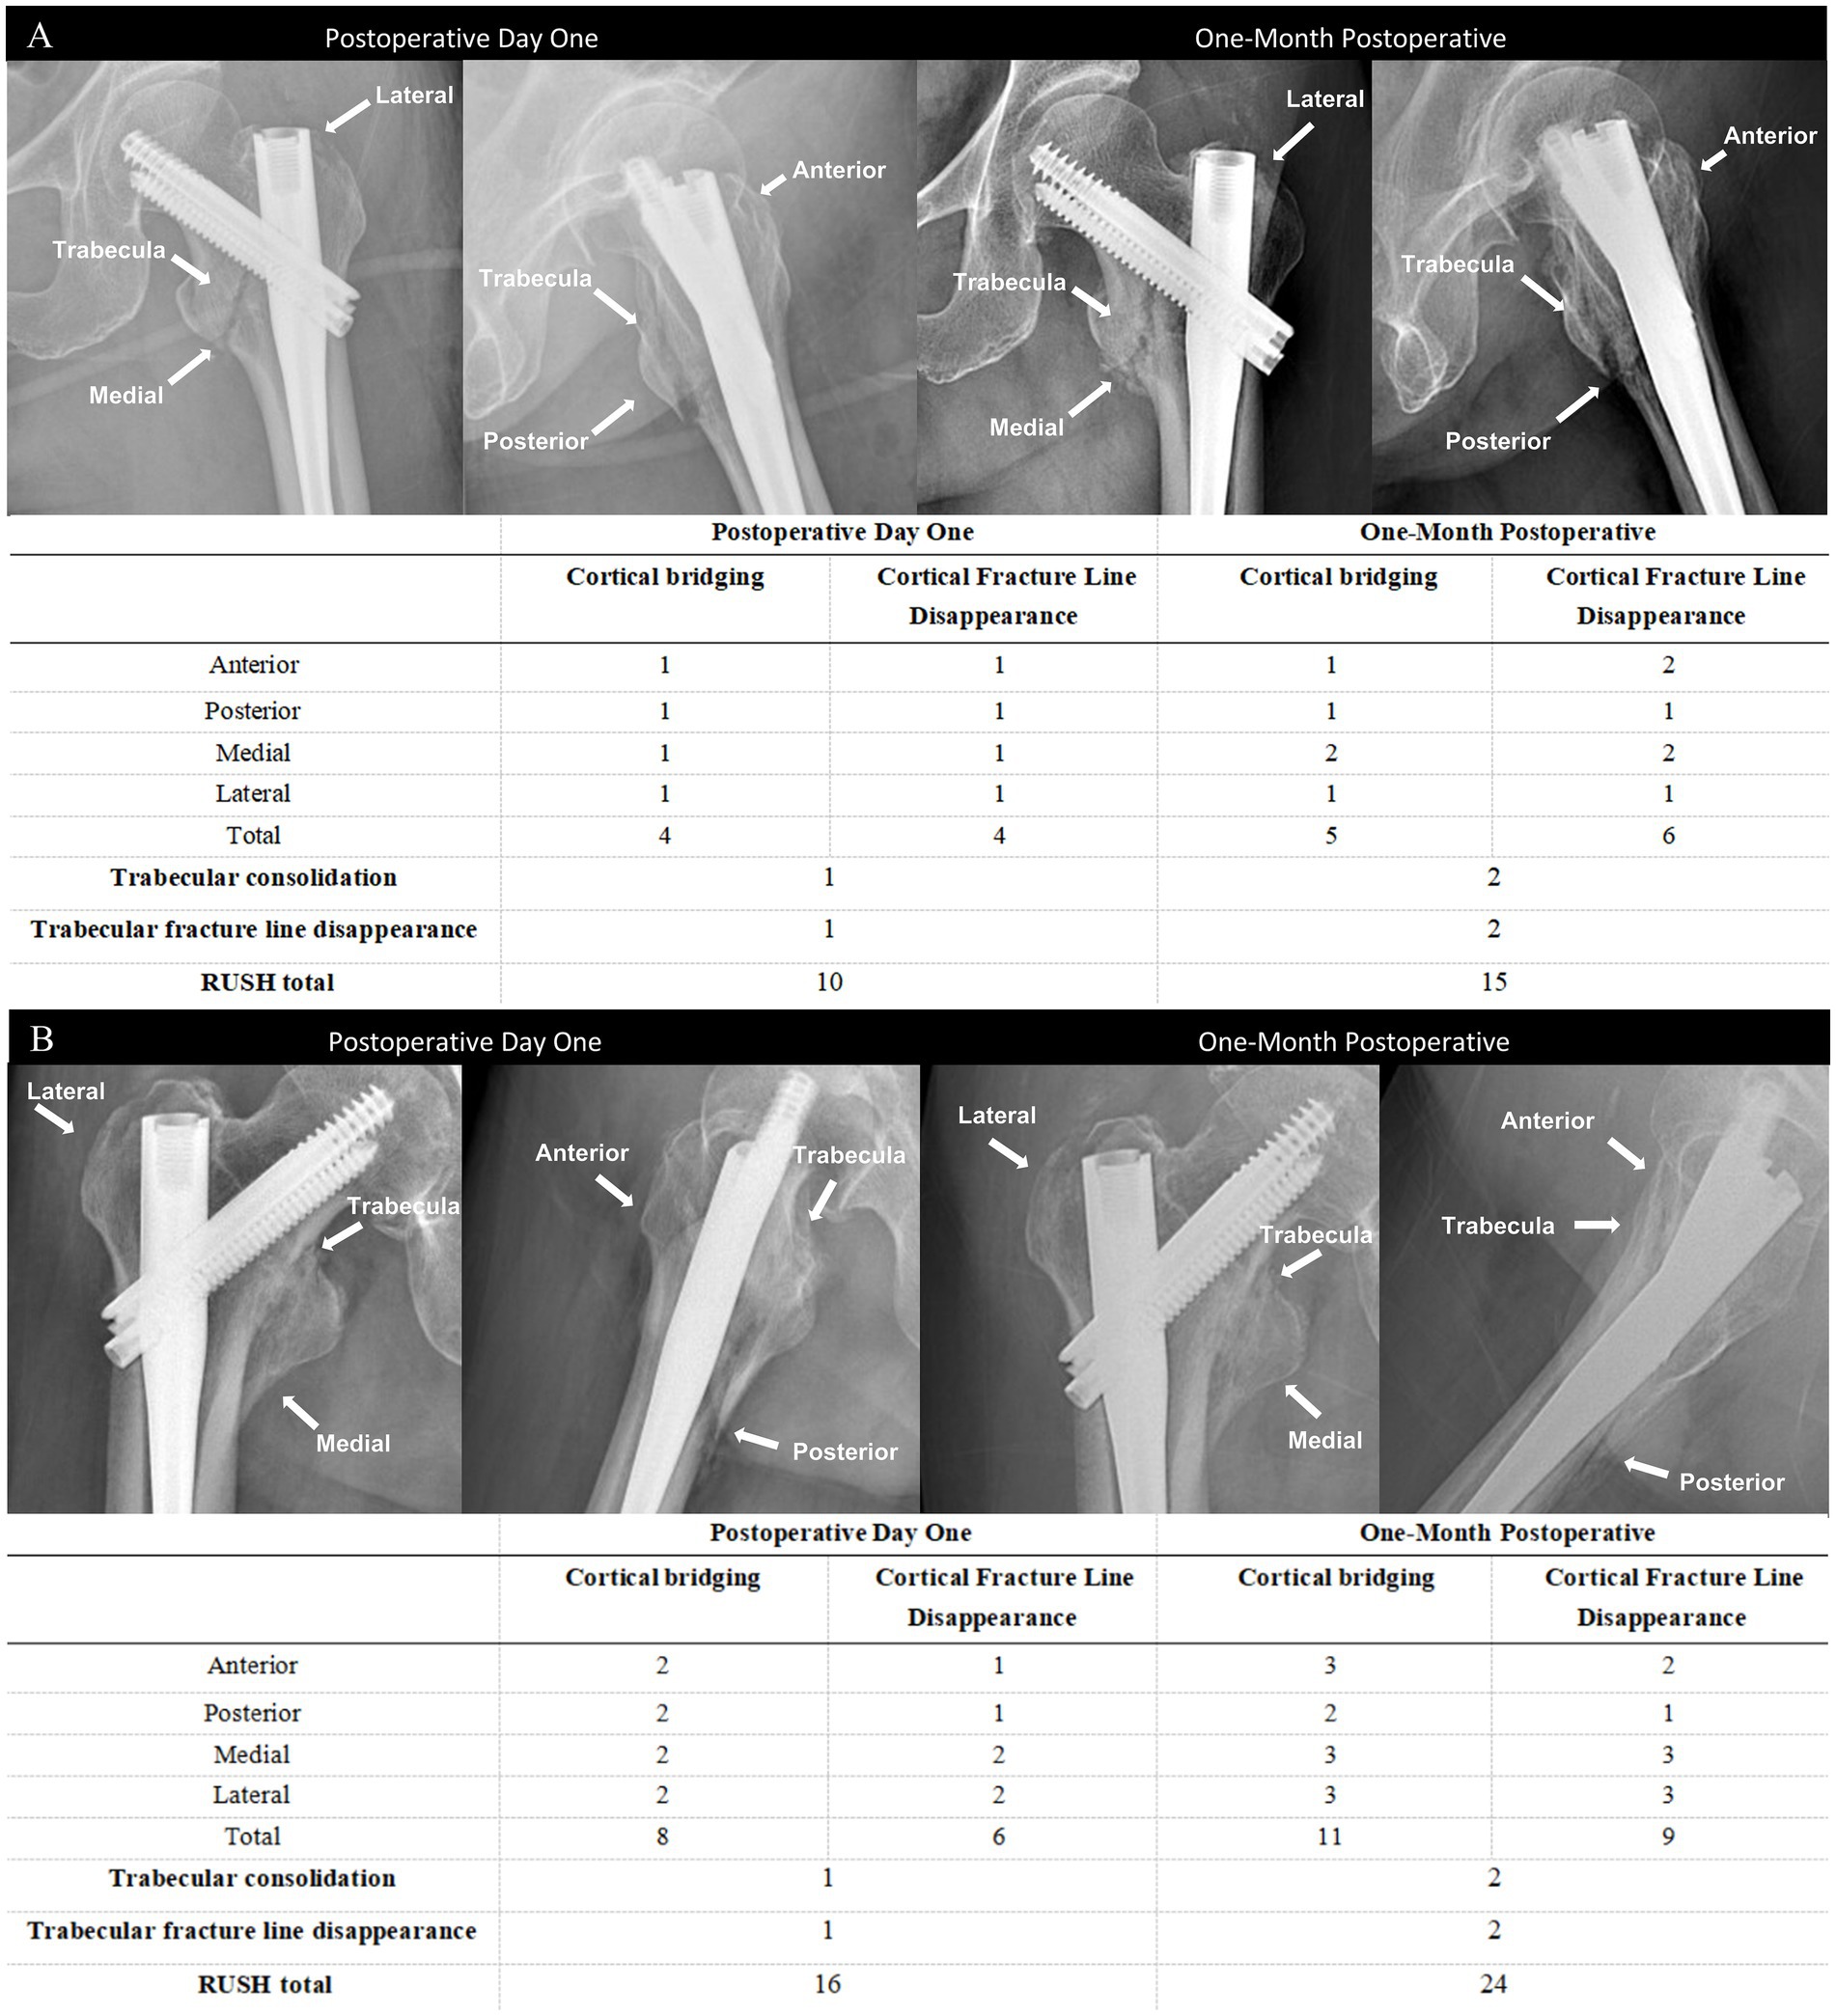

The RUSH score sheet is completed by each reviewer, with the score based on four evaluated components: cortical bridging, cortical fracture disappearance, trabecular consolidation, and trabecular fracture disappearance. The cortical bridging index score ranges from 4 to 12 points, as each of the four cortical bones is scored individually on a scale from 1 to 3. Similarly, the cortical fracture disappearance score ranges from 4 to 12 points, as determined by the visibility of fracture lines across the four cortices. The two trabecular indices are each scored from 1 to 3, reflecting callus formation and trabecular fracture line disappearance, respectively. Therefore, the total RUSH score ranges from 10 to 30 points. As shown in the representative radiographs (Figure 2), two different patients illustrate the variability in RUSH scores applied in the evaluation of fracture healing. The postoperative day 1 radiograph is associated with a low RUSH score (12), while the 1-month postoperative radiograph demonstrates a high score (25), thereby highlighting the progression of healing as captured by the scoring system.

Figure 3. Anteroposterior and lateral radiographs obtained at postoperative day 1 and at 1 month in two patients with relatively slow (A) and fast (B) fracture healing, along with the corresponding RUSH scores.